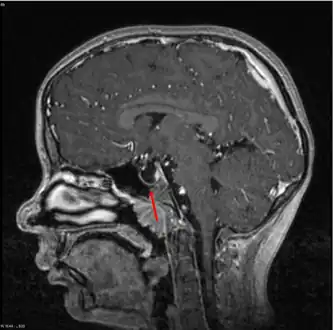

-

Empty sella- MRI Scan of the brain, sagittal T2-weighted -

Empty sella in MRI

The diagnosis of empty sella syndrome, done via examination (and test), may be linked to early onset of puberty, growth hormone deficiency, or pituitary gland dysfunction (at an early age).[2] Additionally there is: